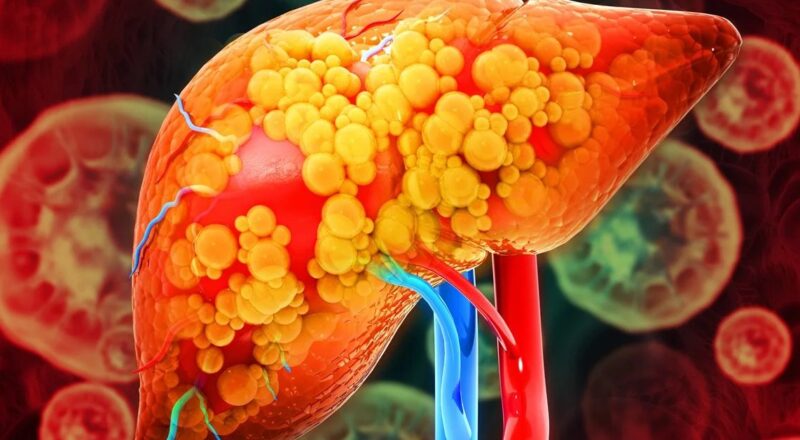

Continue lendoGordura no fígado: entenda os sintomas que esteatose hepática pode causar

A esteatose hepática, popularmente conhecida como gordura no fígado, é uma condição cada vez mais comum e que merece atenção. Embora muitas vezes seja silenciosa, […]